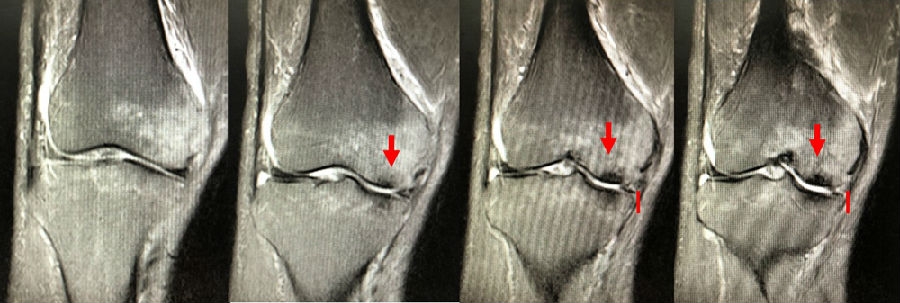

病例3:男,70岁,主诉右膝关节疼痛1年余。查体右膝无肿胀畸形,膝活动度0-120°,内侧间隙压痛。

已经累及44%的股骨内侧髁病变,半月板轻度突出,内侧后角水平撕裂

MRI上深度>20mm

治疗选择保守还是手术?

保守治疗4个月后复查

保守治疗后效果欠佳,坏死范围扩大、塌陷

翻修手术选择截骨矫形还是单髁置换?

最终选择截骨矫形

术后1年1个月

术后2年1个月拆钉

内侧半月板突出未见明显进展

(3)Koshino Ⅲ期 SONK

需在考虑5个因素的基础上,同时兼顾考虑年龄、性别和活跃程度,分别选择用膝关节镜+自体骨软骨移植术(当患者下肢力线内翻<3°时)膝关节镜+HTO术+微骨折术、膝关节镜+HTO+坏死区病灶刮除+自体植骨术或单髁置换术。